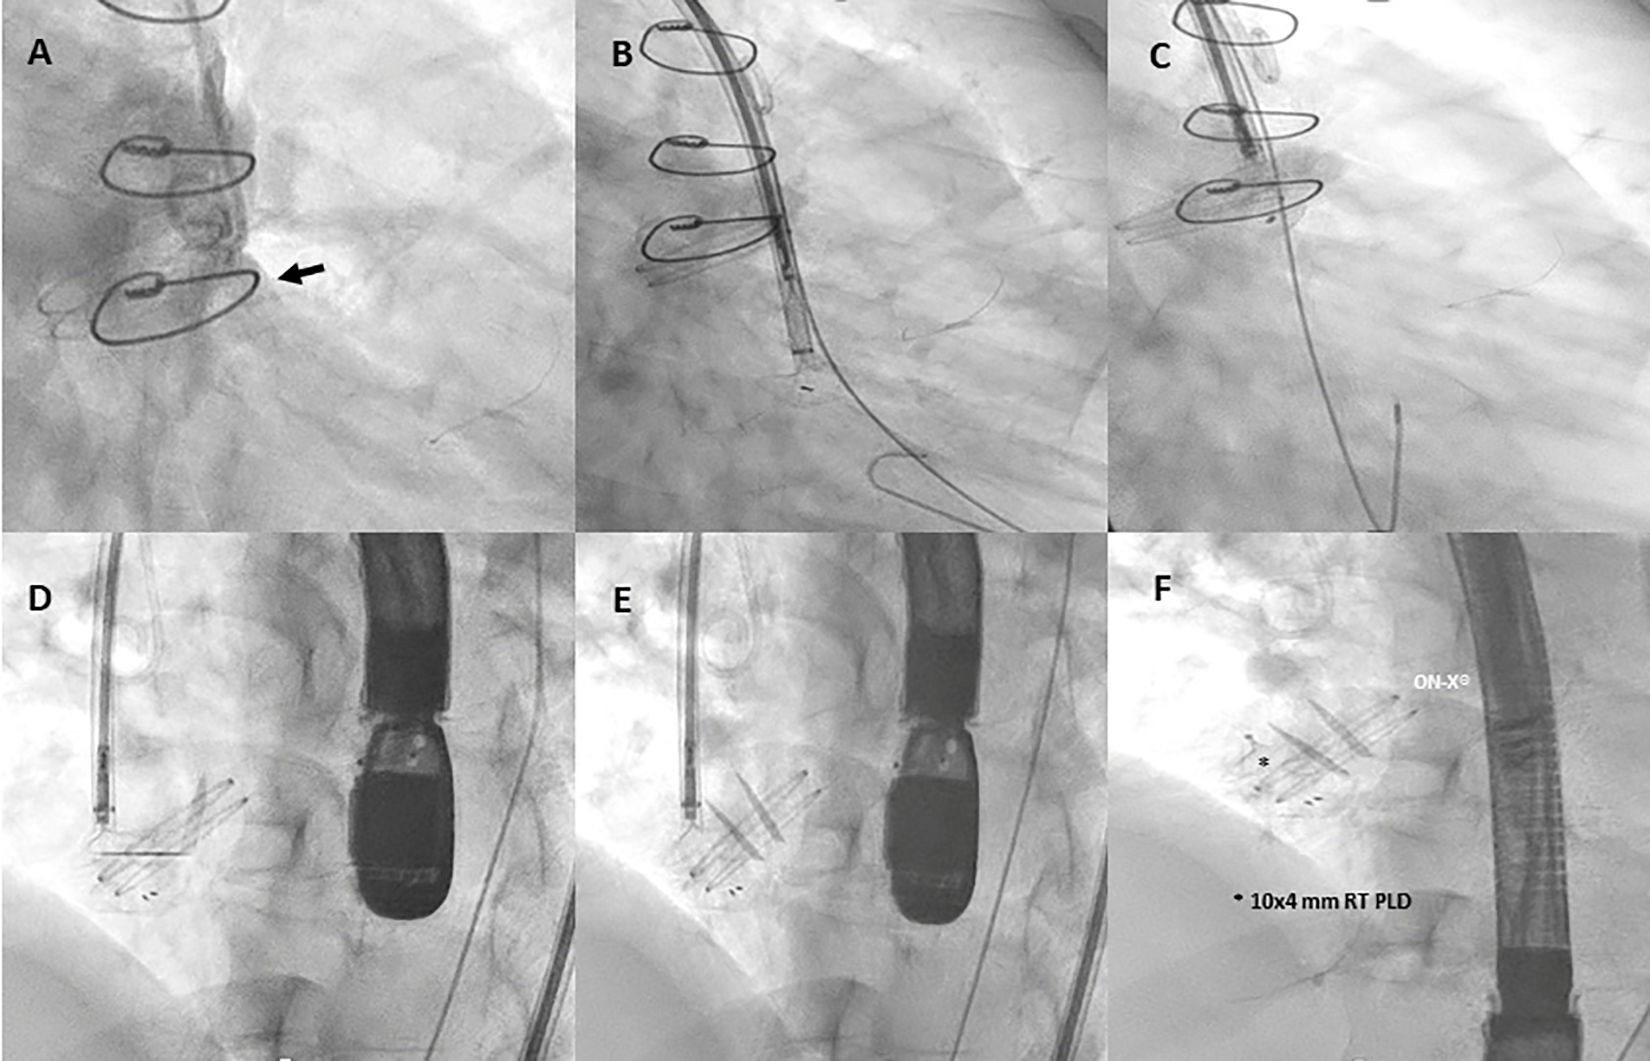

The procedure was performed in March 2024 under general anesthesia with TEE and angio-fluoroscopic guidance. A hydrophilic guidewire crossed the PVL and was replaced with an Amplatz Super Stiff™ wire. An 8-Fr delivery sheath was advanced, and a 10 mm × 4 mm Occlutech paravalvular leak device (PLD) was successfully deployed, achieving significant leak reduction without prosthetic interference (Figure 4, Supplementary Figure 1). Post-procedure imaging confirmed device stability with a trace-mild residual leak (Supplementary Figure 2). The patient was discharged on postoperative day 3 in better clinical conditions.

Figure 4

Fluoro-angiography procedural steps. (A) Right anterior oblique aortography by pigtail 6-Fr showing PVL regurgitation (black arrow). (B,C) The left disc of a 10 mm × 4 mm rectangular twist (RT) PLD (Occlutech, Helsingborg, Sweden) is opened into the left ventricle through an 8-Fr dedicated delivery sheath (Occlutech ODS III) across the leakage, with a buddy wire (black arrowhead) at its site; (D–F) 10 mm × 4 mm RT PLD successfully deployed and released within the leak without interfering with normal leaflet movement of the On-X® prosthetic aortic valve.